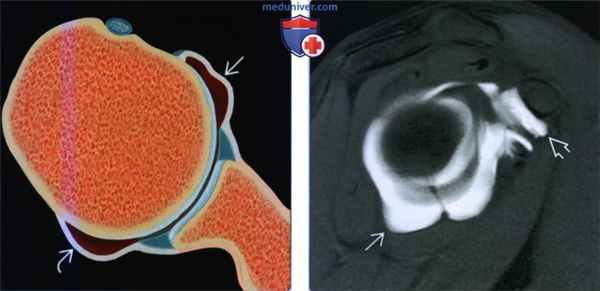

(Слева) На рисунке показана растянутая передняя и задняя капсула без разрыва губы, как наблюдается у пациентов с разнонаправленной нестабильностью. Разнонаправленная нестабильность часто является семейным заболеванием.

(Справа) На косой сагиттальной МР-артрограмме Т1ВИ визуализируется растянутая передняя, задняя и нижняя капсула. Кроме того, наблюдается растяжение капсулы ротаторого интервала. Упражнения на усиление ротаторной манжеты и восстановления оптимального нейромышечного контроля могут ослабить симптомы.2. МРТ при разнонаправленной нестабильности плечевого сустава: